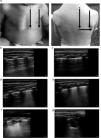

El protocolo de adquisición de imágenes incluyó la evaluación de 10 zonas pulmonares (5 en cada pulmón), obteniendo un vídeo de 10 s de duración en cada zona (fig. 1). Todas las imágenes se archivaron en soporte digital para su análisis posterior. Las imágenes se analizaron en orden aleatorio y sin disponer de los datos clínicos del paciente para asegurar una valoración objetiva y ciega. En cada zona pulmonar se valoraron 3 componentes diferentes de la enfermedad pulmonar en la BA: anomalías de la línea pleural (AP), extensión del síndrome intersticial (SI) y presencia de consolidaciones subpleurales (CS). Las AP valoradas fueron engrosamiento o pérdida del deslizamiento pleural normal; se puntuó como 0 (ausencia de cualquier anomalía) y 1 punto (presencia de cualquier anomalía) para una puntuación máxima de 10 puntos. La presencia de SI se puntuó 0 (patrón normal con predominio de líneas A), 1 (SI con líneas B confluentes definidas como 3 o más líneas B por espacio intercostal o aspecto de pulmón blanco en 1 espacio intercostal) o 2 (SI con líneas B confluentes definidas como 3 o más líneas B por espacio intercostal o aspecto de pulmón blanco en 2 espacios intercostales adyacentes) para una puntuación máxima de 20 puntos. Las CS se puntuaron 0 (ausentes), 1 (una consolidación <1cm) y 2 (consolidaciones >1cm o CS múltiples) para una puntuación máxima de 20 puntos. El score global (ScECO) se calculó como la suma de las puntuaciones de cada zona individual. Así la puntuación máxima posible fue 50 (rango 0-50) (fig. 1).

a) Protocolo de adquisición e interpretación de la ecografía pulmonar. Las áreas exploradas se señalan con números. La puntuación de la ecografía se indica en las imágenes identificadas con letras. En las imágenes se muestra la puntuación asignada a cada anomalía detectada. b) Pulmón normal: 0 puntos. c) Engrosamiento pleural. Puntuación SCORE: 1 punto. d) SI focal. Puntuación SCORE: 1 punto. e) SI difuso. Puntuación SCORE: 2 puntos. f) CS < 1cm. Puntuación SCORE: 1 punto. g) CS > 1cm. Puntuación SCORE: 2 puntos.

CS: consolidaciones subpleurales; SI, síndrome intersticial; 1: área anterior paraesternal; 2: área anterior axilar anterior; 3: área posterior línea axilar posterior; 4 área posterior paravertebral; 5: área posterior infraescapular.